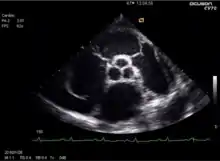

![]() يظهر في الوسط الصمام الأبهري ويبدو عليه تضيق حاد بسبب داء قلبي رثوي. الصمام محاط بالشريان الأبهر، كما يظهر الجذع الرئوي في أسفل اليمين والشريان التاجي الأيمن (مقطوع طوليا) في أسفل اليسار والشريان التاجي الأيسر الرئيسي في اليمين. يظهر في الوسط الصمام الأبهري ويبدو عليه تضيق حاد بسبب داء قلبي رثوي. الصمام محاط بالشريان الأبهر، كما يظهر الجذع الرئوي في أسفل اليمين والشريان التاجي الأيمن (مقطوع طوليا) في أسفل اليسار والشريان التاجي الأيسر الرئيسي في اليمين. | |

صدى القلب

يمكن عن طريق فحص ما يُسمّى بصدى القلب (بالإنجليزية: Echocardiography) والذي يعتمد الموجات فوق الصوتية مشاهدة تكلسات شُراف الصمام الأبهري، كما يمكن بتقنية دوبلر تحديد سرعة تدفق الدم خلال الصمام الأبهري، وبطريقة حسابية تعتمد مبدأ بيرنولي تحديد مدى تضيق الصمام، وحتى حساب المساحة المتبقية من مقطع الصمام، أو تحديد فرق الضغط قبل الصمام وبعده.[13]

من ناحية أخرى فإن نفس الفحص أي صدى القلب يعطي تقديراً لحجم البطين الأيسر ولتضخم البطين الأيسر، كما أن حساب الكسر القذفي يعطي تقديراً لقوة العضلة القلبية، وبالتالي مدى الضرر الناجم عن تضيق الصمام. ويعتبر هذا الفحص الأقل إزعاجاً للمريض وهو فحص غير باضع.[13]